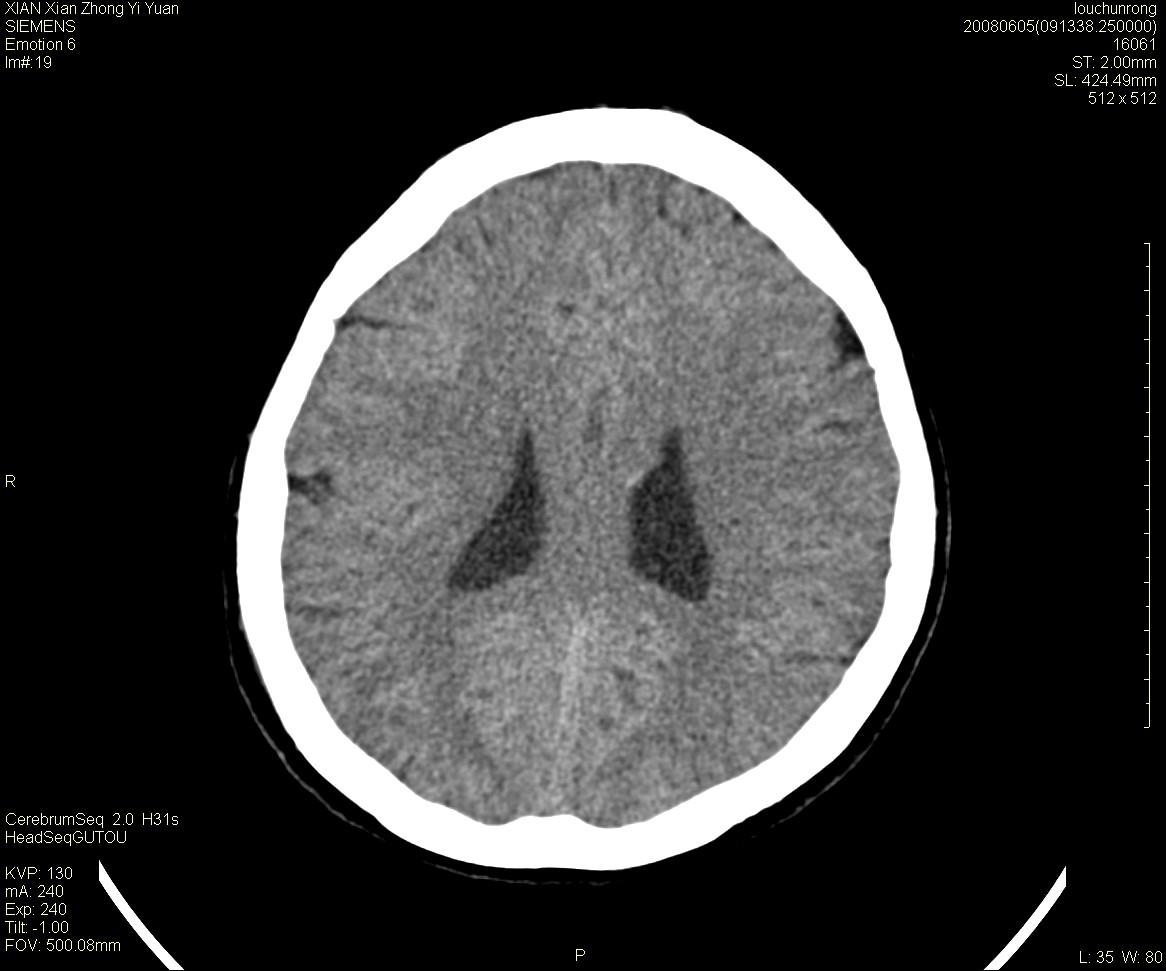

标题: CT13860:F52Y,,头外伤致头晕半天,以前无不适。 [打印本页]

标题: CT13860:F52Y,,头外伤致头晕半天,以前无不适。

层厚2mm。

左侧侧室内血管异常增粗,考虑血管变异或血管瘤可能,余未见异常

大家看左额叶大脑镰旁高密度影

两侧脑室体部距离增宽,胼胝体发育不良?

中线附近、枕叶近枕骨处及脑内多发点条状强化影,考虑血管异常?

大脑大静脉池内的密度不均,双侧脑室增宽,我看右异常这块。战友们看看

侧脑室前角变形、变窄,考虑侧脑室粘合;余未见明显异常。